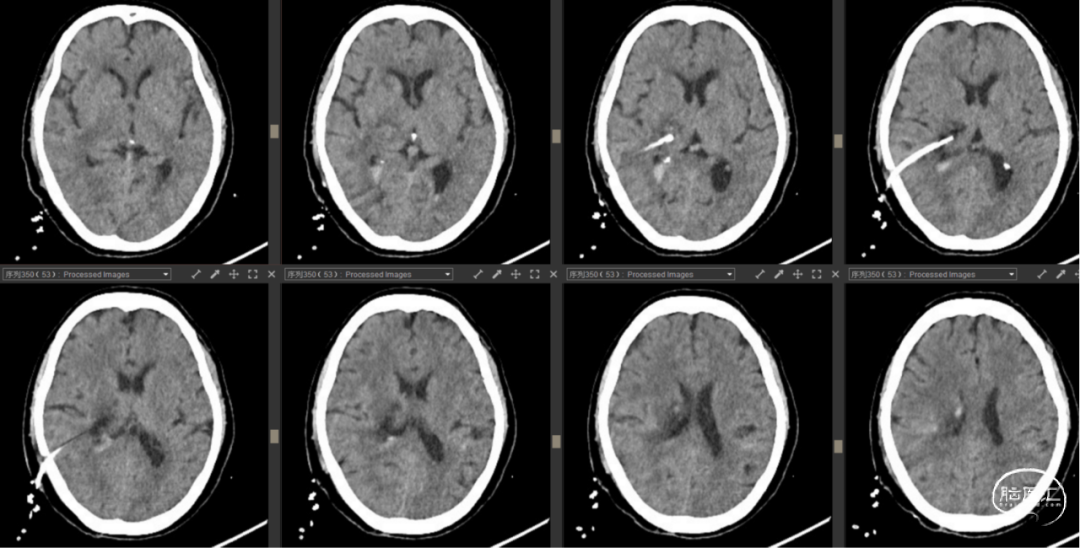

病例4

![]()

患者阳某,女,65岁,因“头晕伴左侧肢体乏力1.5小时”入院2023-07-31入院。

查体:神志嗜睡,GCS评分13分(E3V5M5),呼唤睁眼,无失语,对答切题,构音含糊,双瞳孔等圆等大,直径为2.5mm,张口及伸舌检查不配合,左侧肢体肌力0级,右侧上下肢体5级,四肢肌张力正常。左侧巴氏征(+)。

检查:2023年7月31日急诊头颅CT提示:右侧丘脑出血破入右侧脑室。

既往发现有“高血压”,未规范服药治疗;2年前胰腺手术史,具体不详。

诊断:

1. 右侧丘脑出血破入脑室

2. 高血压病3级(极高危)

术前讨论及手术指征:出血量虽然不多但血肿破入侧脑室引起意识障碍、肢体肌力0级。丘脑血肿压迫静脉以及分泌含铁血黄素可导致进一步水肿损害脑组织的可能,建议尽早排除血肿有减残的可能性。家属经过商议后积极要求微创术式。

手术方案:经颞叶入路机器人辅助导航右侧丘脑血肿穿刺引流。

![]()

2023年7月31日

![]()

术后3天CT